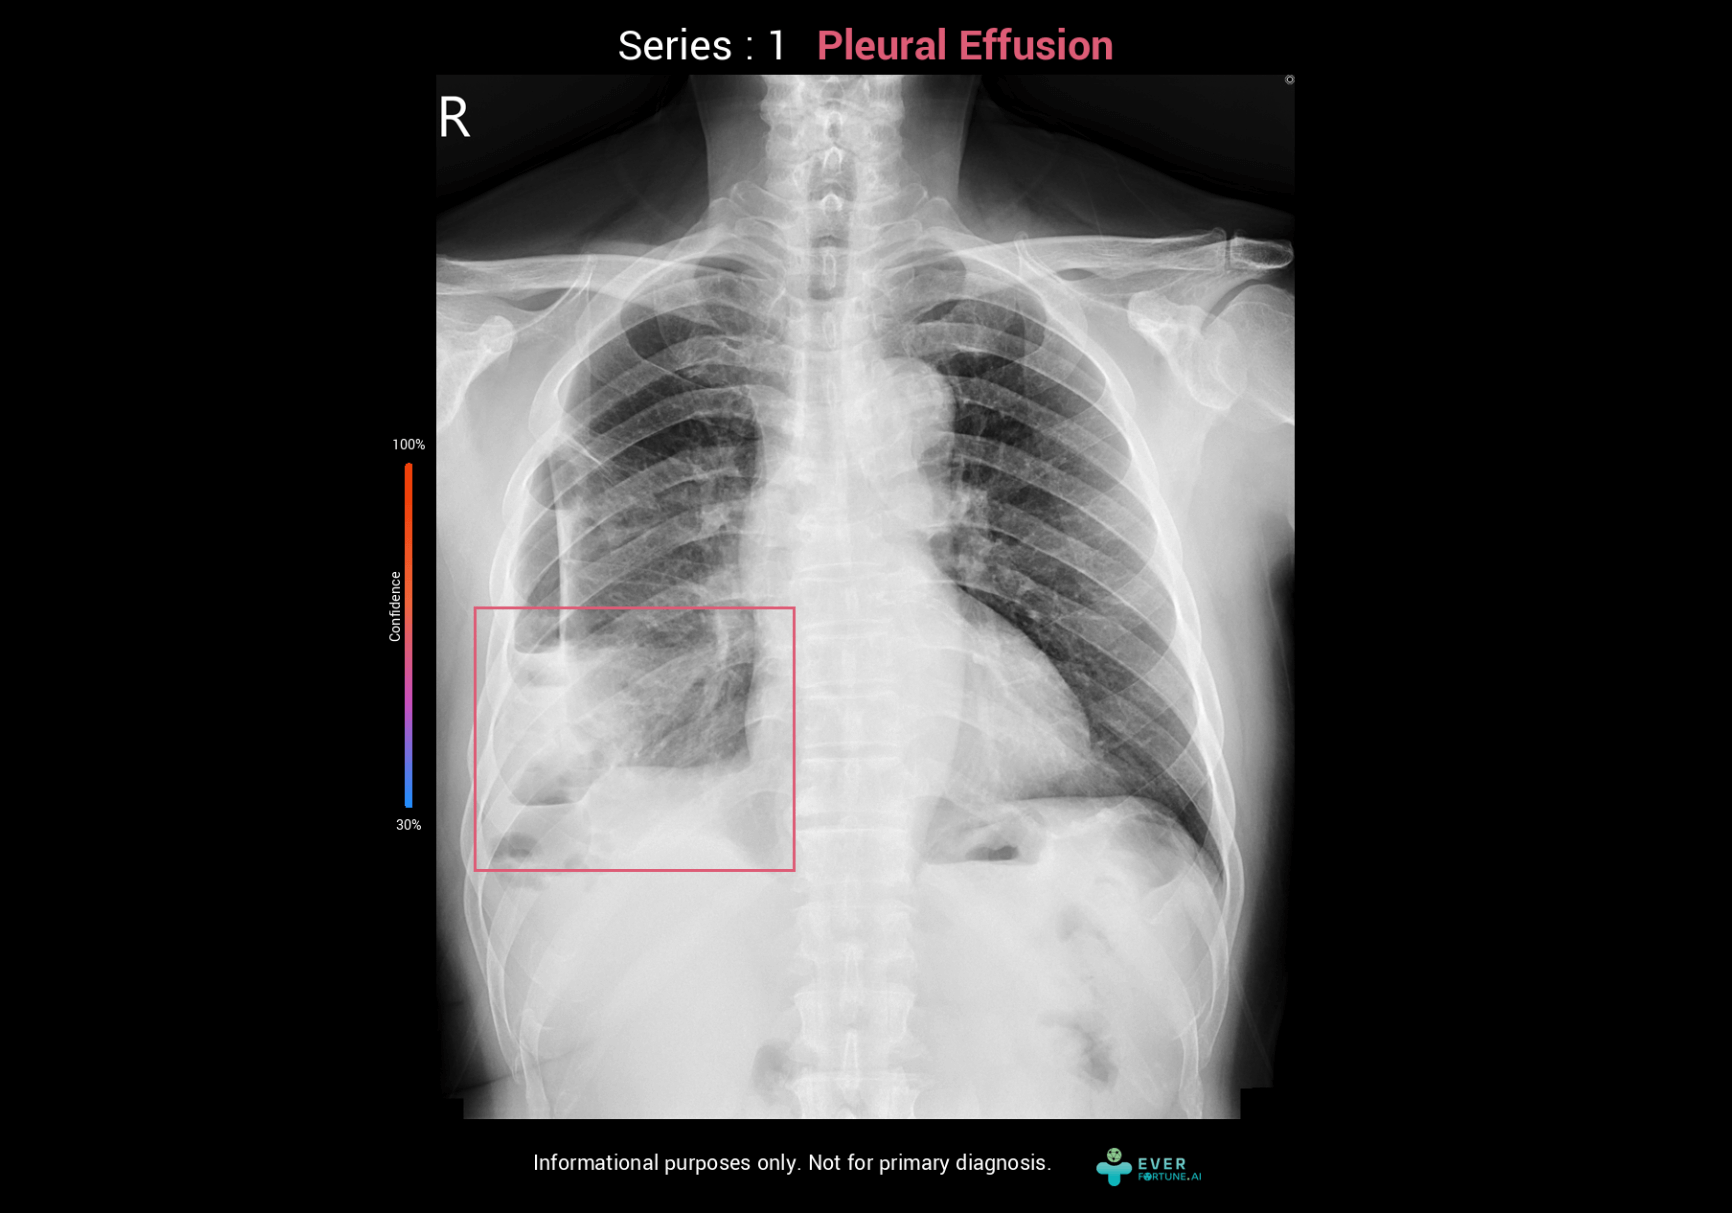

Plerual Effusion Assessment System

ChestSuite XR Assessment System

Identify 15 abnormal finding in chest X-ray images with heart, lungs and bones. The system as a pre-read assistance enable a quick interpretation and faster decisions